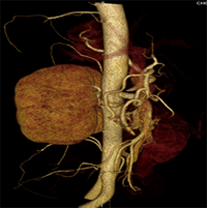

如上圖所示,相鄰的三張軸位圖像未見明顯異常,根據傳統軸位圖像很難得到準確的臨床診斷。

同一病人利用容積數據進行三維處理后,高品質MPR和三維圖像上則清晰顯示了縱向排列的腹腔干與腸系膜上動脈相鄰近,血管發生變 異,近端血管閉塞,為臨床提供了精確的診斷信息。